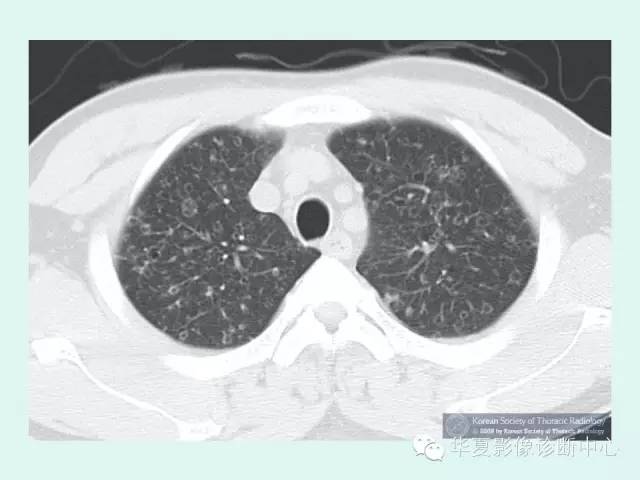

高分辨CT(HRCT)不仅对该病的鉴别诊断有意义,而且对判断该病的严重程度具有一定意义。病变通常分布在正常的肺组织中间,虽然在双下肺基底部位可以见到散在病变,但病变多位于上部,呈对称性均匀分布。早期病变主要以边界模糊的小结节阴影为主,有些病例可以见到有空洞形成。结节呈小叶中央性分布,并且伴有壁厚薄不等的囊性改变。随着病变的进展,囊性改变逐渐成为突出表现,这些囊腔大小差异很大,但通常直径小于1cm。囊腔可以为孤立样,也可互相融合,甚至形成肺气肿、气胸的表现。自发的出现小结节、空洞和囊性化是肺朗格汉斯组织细胞增生症较为特征性的改变。

1、双肺弥漫分布结节 是PLCH早期影像表现,直径约1~10mm大小,典型者直径1~5mm,病灶多两侧对称分布,中上肺野为主,肺基底部、肋膈角附近也可有少量分布。结节的数量可以是较少,也可以在肺野内弥漫分布不可数。结节边缘不规则为特征性地表现,结节周围为正常的肺组织围绕。

2、囊样病变 是PLCH的最常见的CT表现,通常直径小于10mm,但也可以达到20mm。囊样病变通常同结节并存,但是也可以是惟一的CT表现。囊样病变主要发生在肺上中野。可表现为圆形或卵圆形的囊变区.也可表现为各种各样的形状,囊样病变的壁可以很薄,仅仅可辨或者表现为厚壁和结节样。